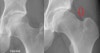

X-ray : Pistol grip deformity

대퇴골의 이상은 pistol grip deformity 같이 AP에서 관찰되는 경우도 있지만, cam 병변이 주로 전면에 위치하는 경우 AP view에서는 정상으로 보일 수도 있기 때문에 Lat 사진에서 평가해야 합니다.

특징적인 소견은 앞뒤 또는 가쪽면에서의 관절간격은 정상이지만 대퇴골두와 목의 편차(femoral head-neck offset)의 소실(cam impingement)과 크로스오버 징후(pincer impingement)가 나타나는 소견입니다.

대퇴골두 절구내 충돌(pure femoral cam impingement) 시에는 앞쪽 대퇴골두 부위의 정상적인 오목형 모양이 소실되며, 그 대신 고관절 굴곡 시 위앞 방향 순(labrum)에 충돌하는 국소 골형성 부위가 존재하여 순파열과 인접 연골마모를 유발하게 됩니다.